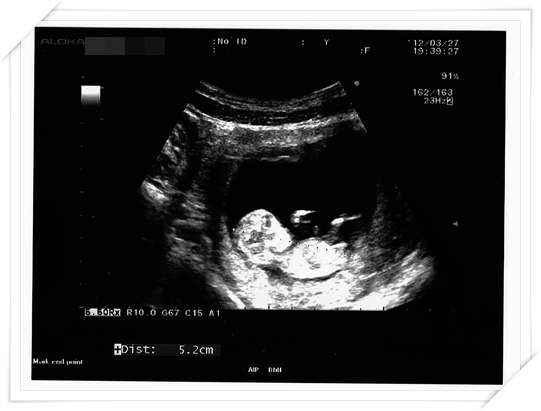

這次產檢 醫生也順便幫我做了頸部透明帶的測量

通常是跟第一期母血唐氏症篩檢一起做的

就是看看唐氏症的機率囉

所以就約好11週半左右去做

居然baby 的手腳都長出來啦!!!!

長的好長 在肚子裡面揮來揮去的 真的好有趣唷!!

醫生也印了超音波照片給我們

Mr.E 直說 這張照片好像小鴨子阿~~~~